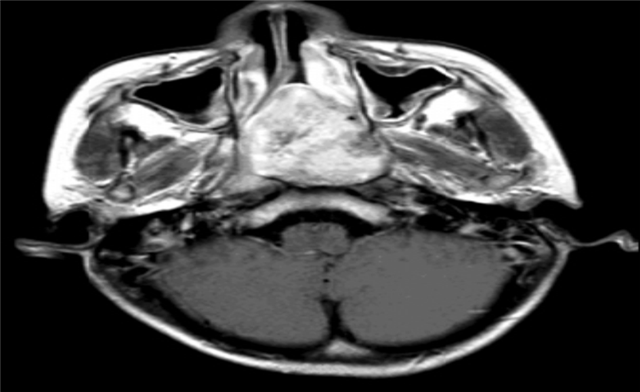

图2 MRI 横断增强:肿瘤信号均匀强化, 边界清(图片来源于医院影像中心)

目前主要通过鼻内镜或者电子鼻咽检查予以初步诊断,最终依赖于鼻咽部CT和MRI来术前诊断。